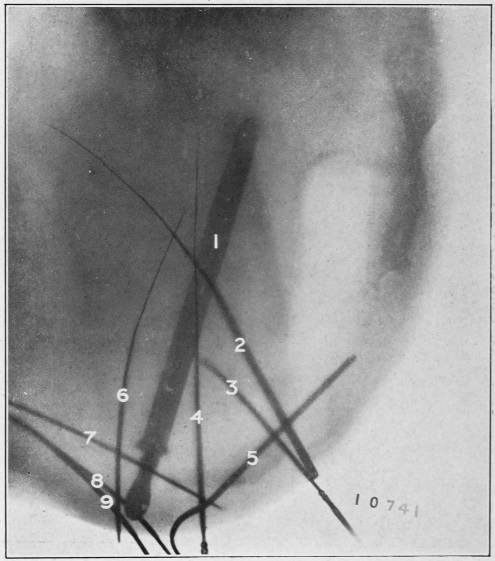

Fig. 1.

A portion of the wall of the rectum has been removed exposing various layers: 1, serous layer; 2, muscular layers; 3, 3, submucous layers; 4, 4, mucous membrane; 5, internal sphincter muscle; 6, external sphincter muscle; 7, circular muscular bands forming the rectum; 8, rectum; 9, sigmoid flexure. (See Fig. 7, showing the longitudinal muscular bands.)

The muscular coat of the rectum consists of two layers: an inner circular and an outer longitudinal band. The inner circular layer of muscular tissue of the rectum forms the internal sphincter muscle; and the outer longitudinal bands merge with those of the external sphincter. The anal orifice is closed or guarded by two strong sphincter muscles, as shown in Figs. 1, 2, and 3. These muscles are abundantly supplied with nerves, of which branches are distributed to the bladder and other adjacent organs, which accounts for the sympathy of these organs and their grave disturbance when disease inheres in the anus and rectum.